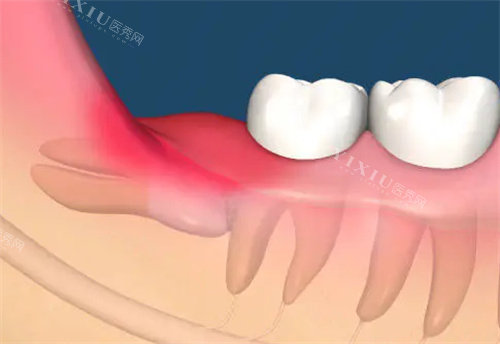

拿着牙片见到主治医生的时候,我心里还是有点忐忑。但医生特别有亲和力,他一边看着牙片,一边给我讲解我的智齿情况,说我的智齿是横着长的,不仅容易反复发炎,还会影响旁边的牙齿,确实得拔掉。他用通俗易懂的语言,把拔智齿的过程、可能出现的情况,还有术后的注意事项都讲得明明白白,还会时不时问我有没有听明白,有没有什么疑问,让我一下子就觉得特别安心。